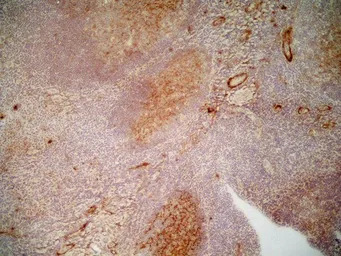

IHC-Fr analysis of human tonsil tissue using GTX76433 CD36 antibody [SMO].